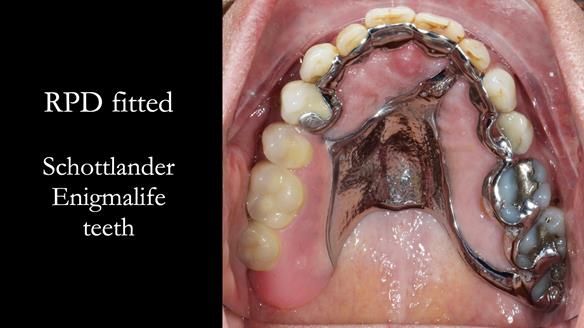

Welcome to Newsletter 64. I'll walk you through the process of providing a Mk 2 metal-based partial denture (RPD), for Ian a retired Veterinary Surgeon aged 78. The RPD was made at an increased vertical dimension and acted as an occlusal stabilisation splint - reducing the wear and bite force on the remaining natural teeth.